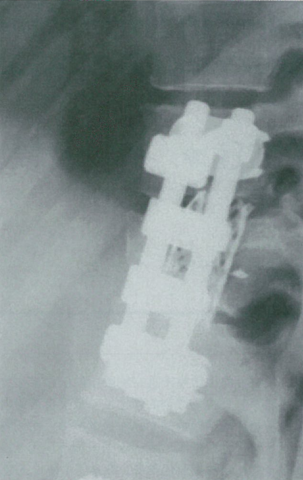

Kaneda及其同事发展了应用带齿椎体板及钉棒连接固定的技术。Kaneda脊柱滑棒系统(KanedaSR™;DePuy Spine,Raynham,MA)由棒和四个皮质骨螺钉构成,可以进行加压和撑开(图2)。

图2 Kaneda内固定系统